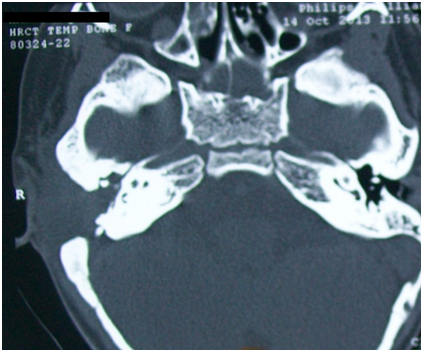

High resolution CT of the temporal bone showed a soft tissue density in attic, aditus and antrum. The dural plate and sinus plate were found to be eroded (Figures 4&5).

Figure 4 HRCT temporal bone (axial view) shows soft tissue density in right middle ear, mastoid air cells. Left middle ear is normal.